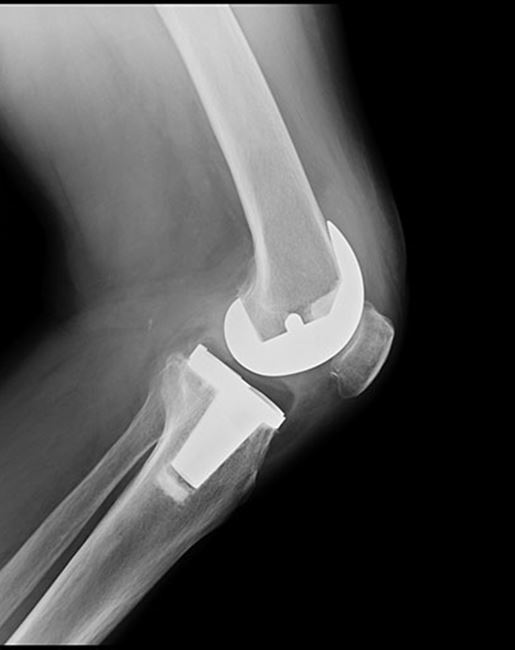

Bilateral Total Knee Replacement Stock Image C003/4806 Science